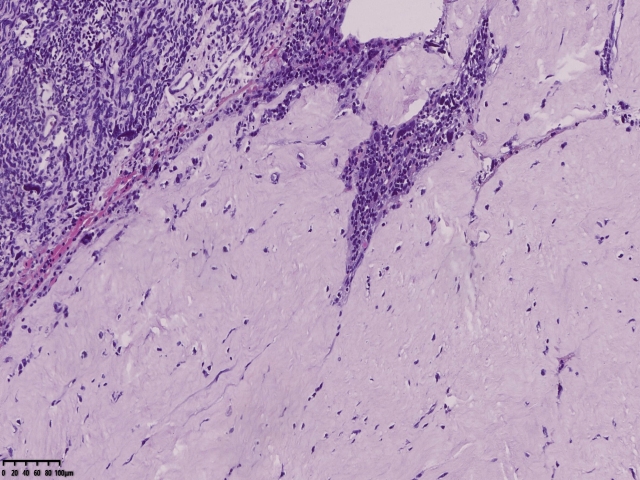

镜下可见肌间可见梭形瘤细胞,细胞核畸形,多核瘤巨细胞。坏死。

坏死?